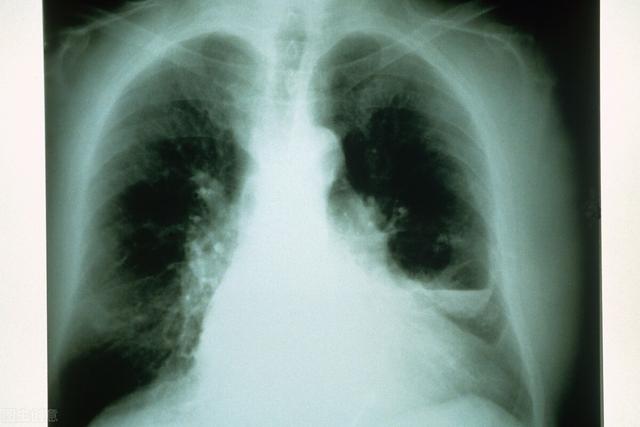

支气管炎多发于老年人 , 一般表现为咳嗽 , 咳痰 , 由于感冒等原因引起支气管炎急性发作时 , 咳嗽加重 , 咳痰增多 , 严重还会出现气喘、气短等;咽喉炎的表现就是咽喉部出现不适感 , 异物感、轻微疼痛等 , 咽喉炎急性发作时咽痛明显 , 可有发热 。

咽喉炎和支气管炎它们的发生部位和致病原因是不一样的 , 咽喉炎是由于患者过于疲劳或者烟酒过度等和病毒、细菌等感染形成的 , 发生部位在咽部黏膜及黏膜下组织;而支气管炎的发生部位在支气管 , 通常是由于细菌或病毒等各种类型的致病菌感染引起的 。

在临床症状上支气管炎和咽喉炎的区别也是很明显的 , 支气管炎会出现低热、畏寒、周身乏力 , 咽喉部发痒 , 刺激性咳嗽 , 胸骨后疼痛等轻微症状;而咽喉炎会咽部干燥 , 灼热 , 吞咽口水疼痛 , 严重的还出现发热、头痛、食欲不振和四肢酸痛等临床症状 。